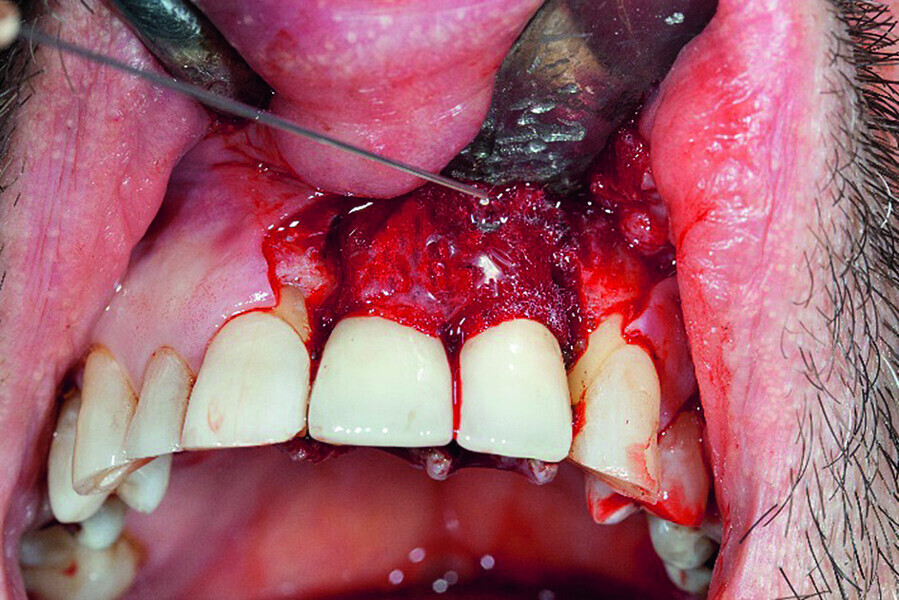

Peri-implantitis therapy